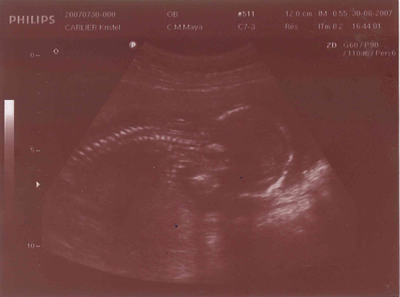

Le 30/08/2007, je mesurais déjà +/- 15 cm